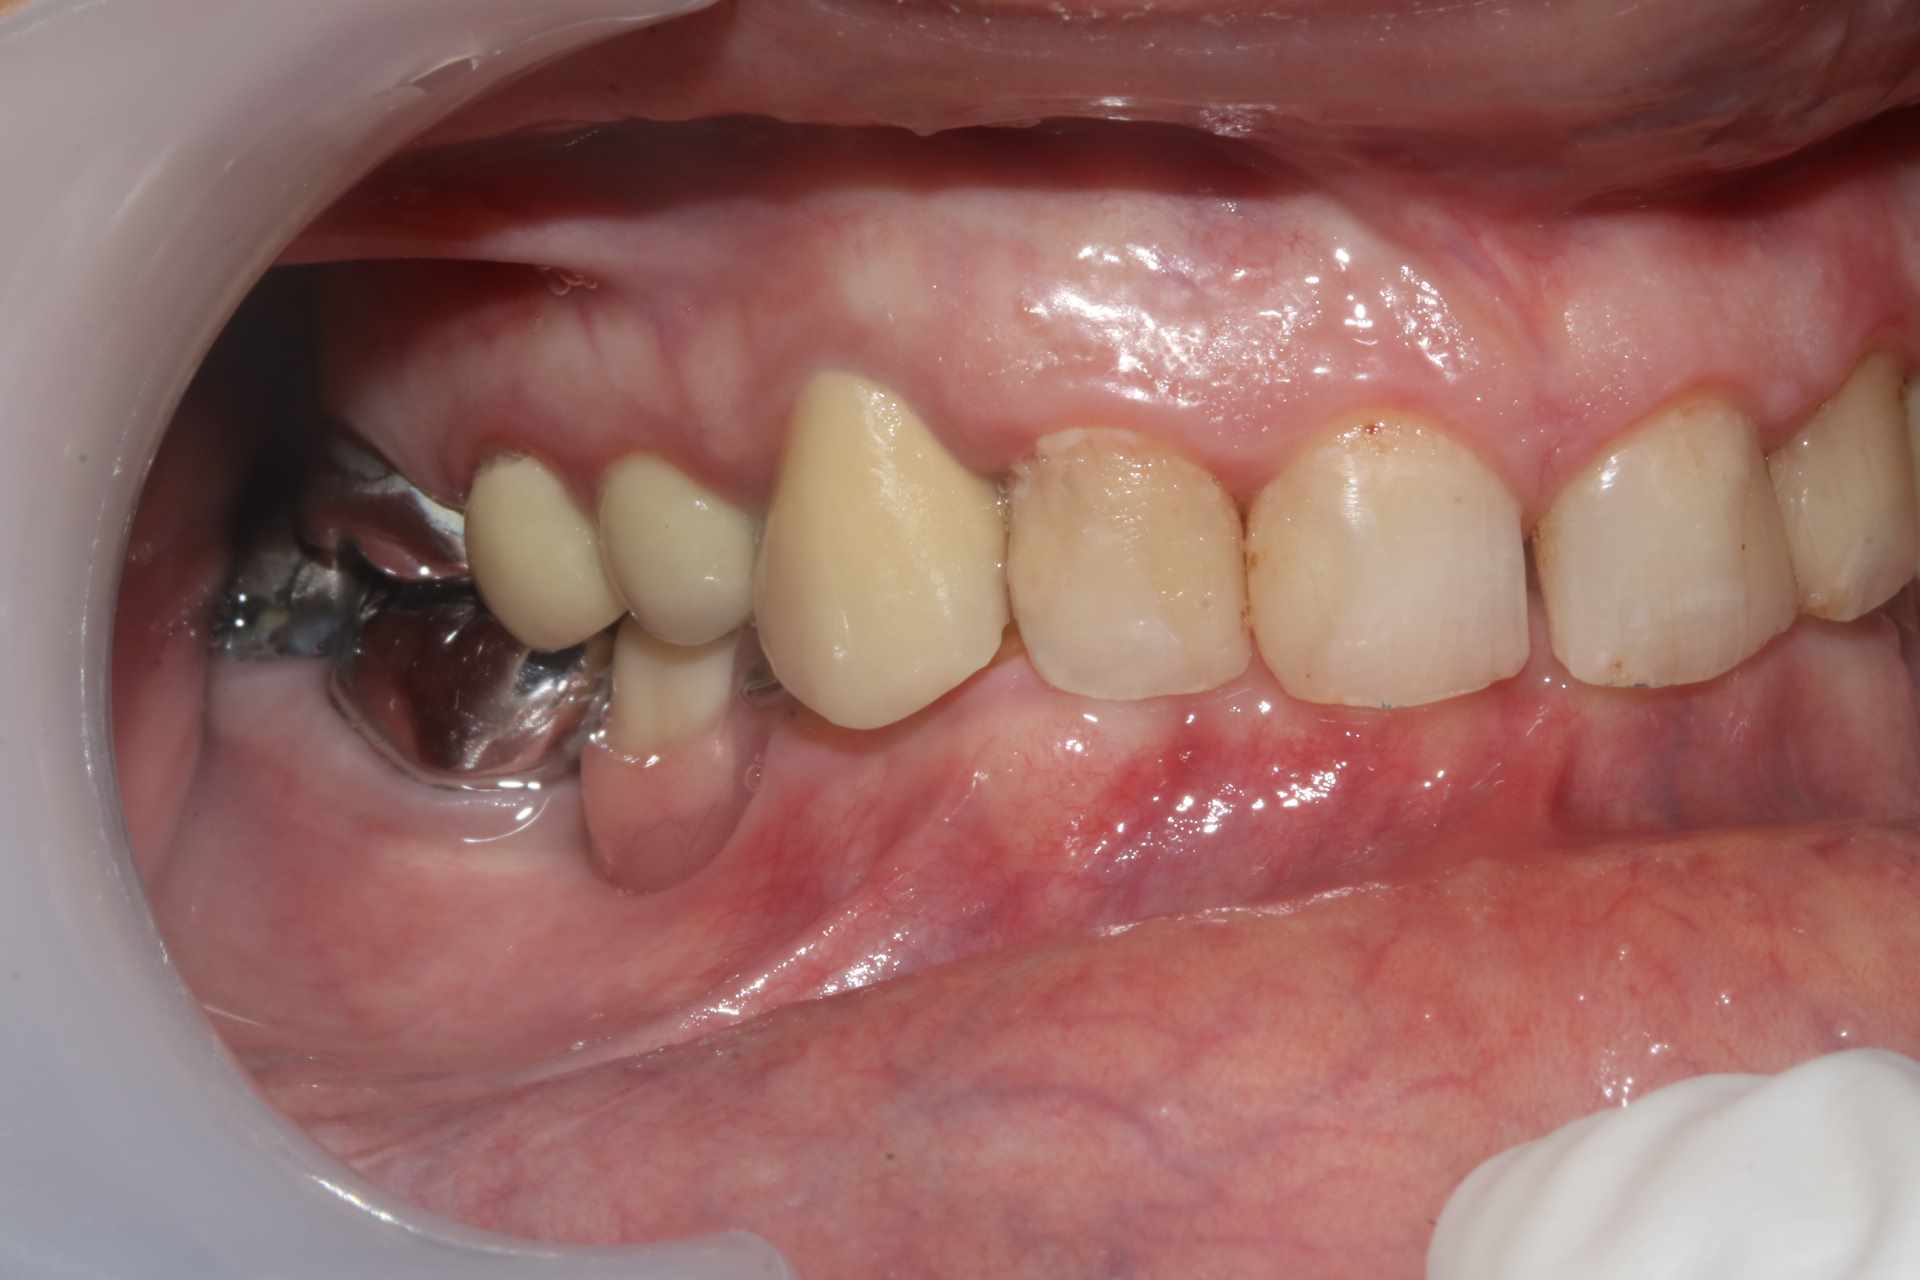

La patiente venait pour 34 35 descellées et 13 mobile. J'en suis encore au stade on traite les urgences avant de s'attaquer vraiment au cas. Vous voulez pas me donner un coup de main ? je ne sais pas trop par ou commencer !

On a une classe 2 2 majeure. ultra verrouillée. Je ne vois pas comment m'en sortir sans augmenter la DV qui a été malmenée par les soins et couronnes diverses a peu près tous en sous occ à mon avis sauf la 13 qui a explosé.

Oui la couronne sur sur 13 c'est une honte, volumineuse et beaucoup trop longue. Je suspecte une couronne faite avec un mordu unilatéral pour expliquer une telle aberration.

Sur 34 35 il y avait des couronnes jumelées qui se sont descellées peu après que la 13 se descellée / fracture.